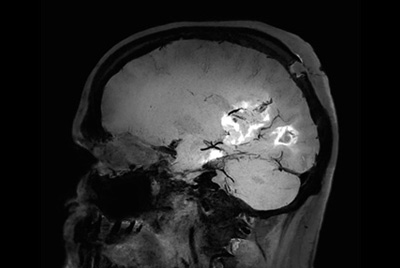

Pediatric brain with AVM